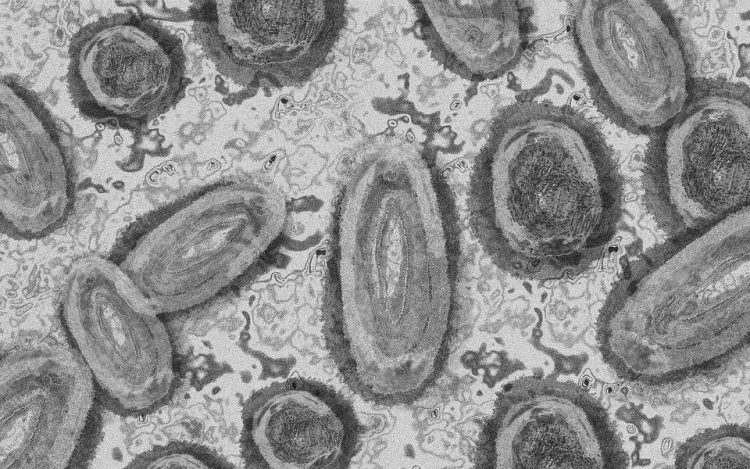

Újabb kilenc, 23-50 éves férfinél igazolták a majomhimlő-fertőzést Magyarországon, ezzel 42-re nőtt a fertőzöttek száma - közölte a Nemzeti Népegészségügyi Központ (NNK) csütörtökön az MTI-vel.

A fertőzöttek július 25. és 31. között majomhimlőre utaló tünetekkel keresték fel a területileg illetékes egészségügyi szolgáltatót, ahol minden esetben mintát vettek majomhimlő gyanúja miatt.

A betegség általános, nem specifikus tünetekkel - lázzal, hidegrázással, izomfájdalommal, hátfájdalommal, fejfájással, fáradtsággal), illetve a nyirokcsomók duzzanatával kezdődik, majd 1-3 nappal a bevezető tünetek után bőrkiütések jelennek meg. A kiütések sok esetben először az arcon, majd a tenyéren és a talpon fordulnak elő, de megjelenhetnek a szájnyálkahártyán, a nemi szerveken és a végbél környékén is - olvasható a közleményben.